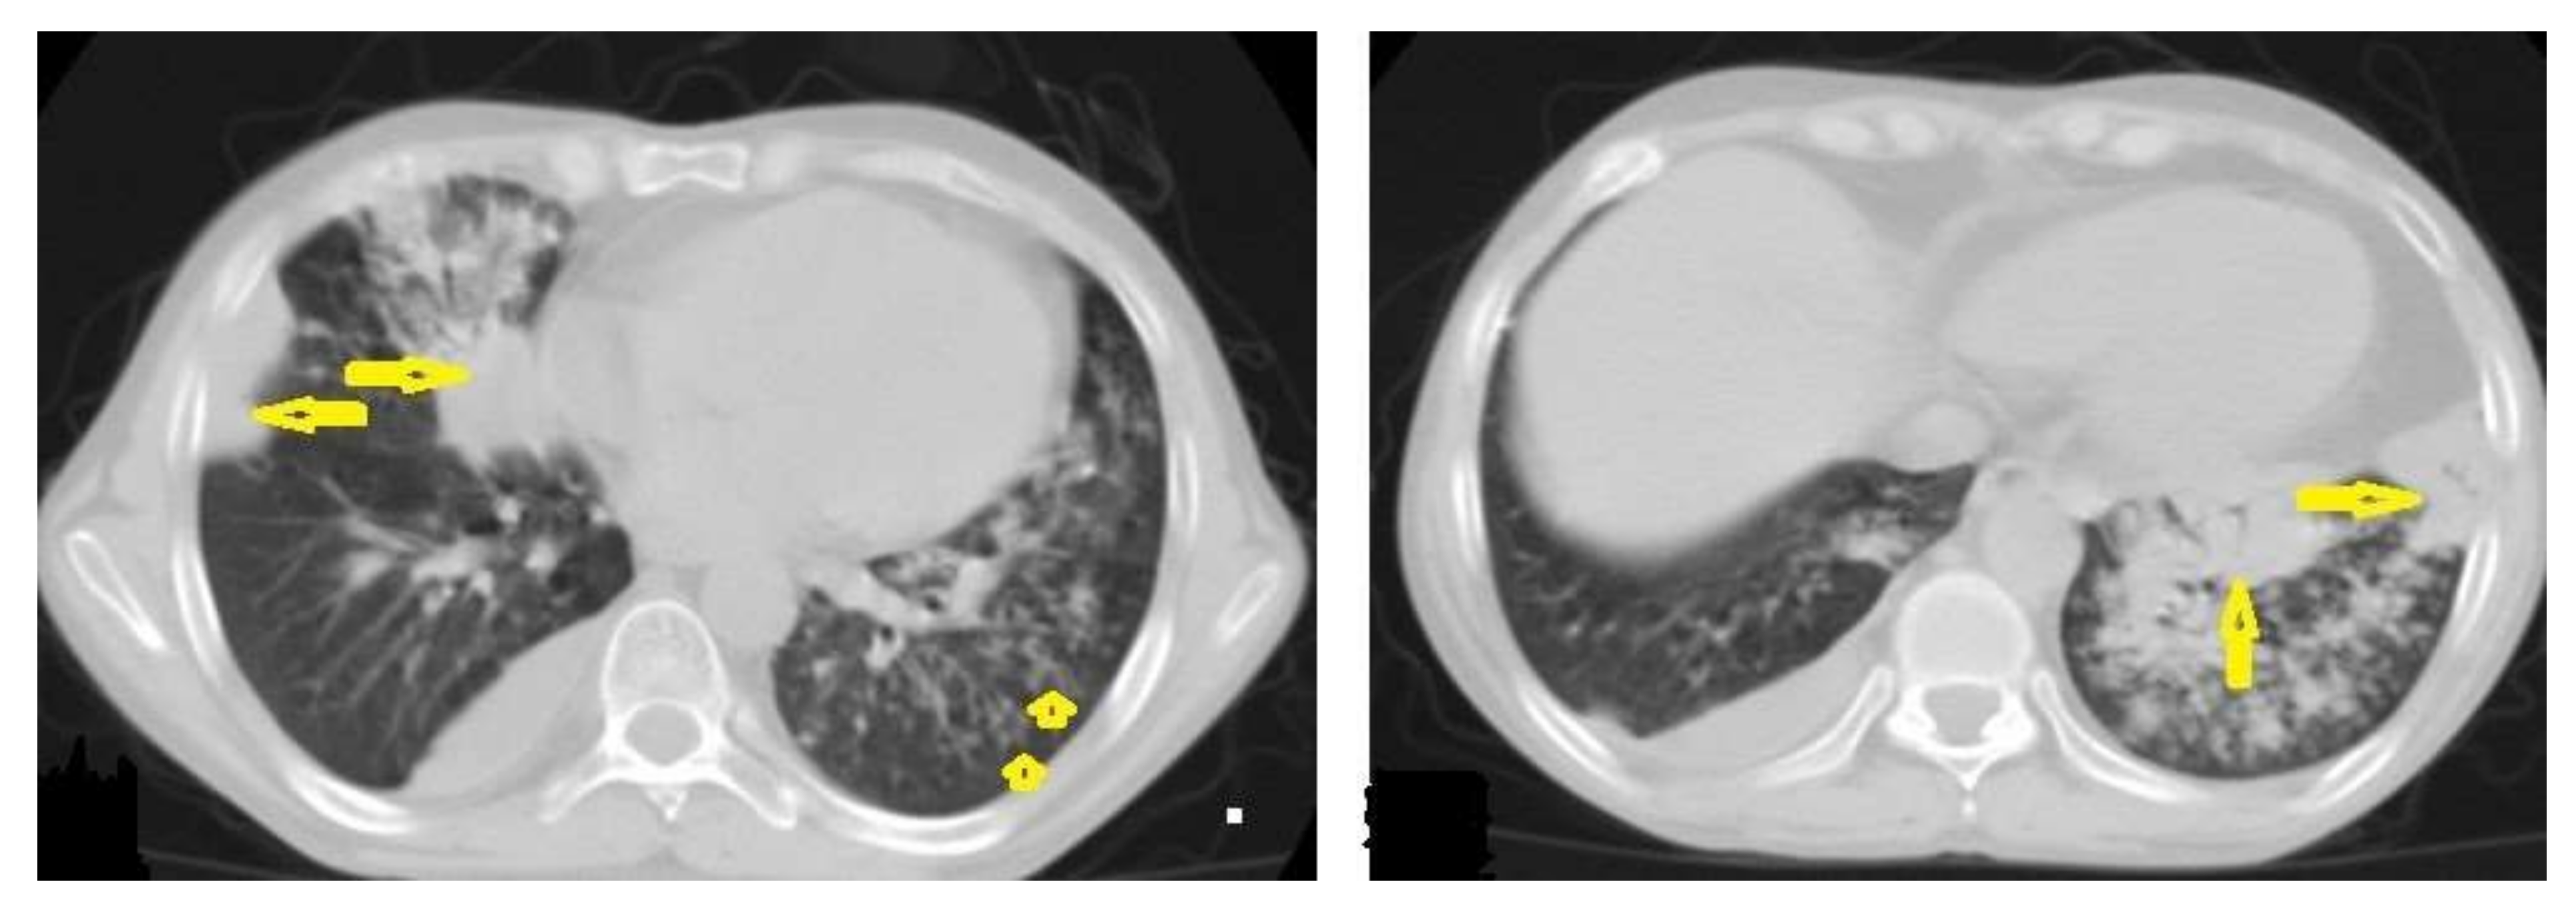

Figure 2. Active TB in a 27-year-old man with extensive endobronchial spread. Selected axial images of chest CT show extensive endobronchial spread characterized by patchy consolidations (long arrows) in the right middle and left lower lobes with tree-in-bud nodules (short arrow) more involved the left lung. Mild right pleural effusion and mild pericardial effusion appear in both images.

• Centrilobular nodules (Figure 4 and Figure 5) occur due to the communication of active TB with the bronchial tree resulting in endobronchial spread. It occurs in most cases of active TB. It appears as centrilobular nodules and a tree-in-bud sign on CT images [1,10]. The tree-in-bud pattern is seen on high-resolution CT images as 2–4 mm centrilobular nodules of soft tissue density that are connected to multiple branching linear structures of the similar caliber, arising from a single stalk. It commonly occurs in the endobronchial spread of TB and is highly suggestive of active TB. However, a tree-in-bud is a CT manifestation of the diverse entities of lung diseases, including TB, cytomegalovirus, respiratory syncytial virus, obliterative bronchiolitis, diffuse panbronchiolitis, cystic fibrosis, airway-invasive aspergillosis, allergic bronchopulmonary aspergillosis, and pulmonary metastasis [18].

• Miliary TB (Figure 6 and Figure 7) appears as innumerable small (1–3 mm) granulomas with random distribution in the lungs and other organs with a predominance to the lung bases due to the gravity-dependent high blood flow. It occurs due to the hematogenous dissemination of mycobacterium tuberculosis bacilli, especially in immunocompromised patients and children [1,13]. Miliary TB is a significant differential diagnosis of pulmonary metastasis from thyroid cancer or others, even in children [19].